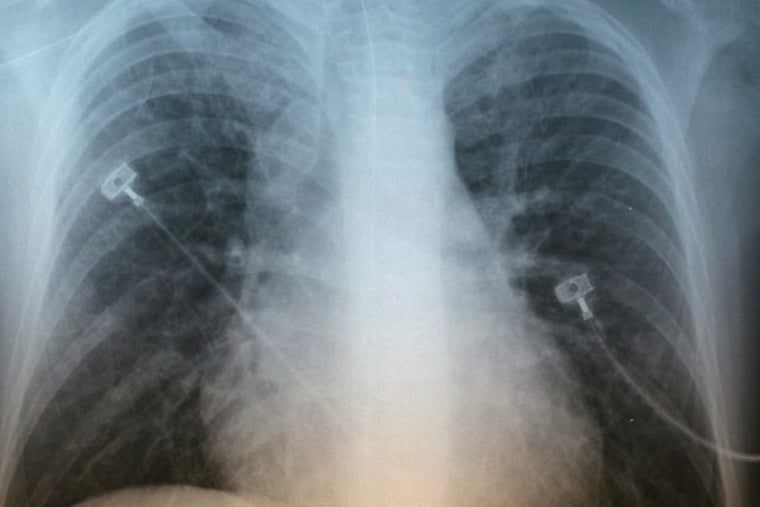

Gelegentliches oder erkältungsbedingtes Schnarchen ist unbedenklich. Regelmäßige Schnarcher sollten sich aber von einem Arzt durchchecken lassen: „Beim krankhaften Schnarchen verengt sich der Rachen stark und es gelangt nur wenig Luft in die Lunge. Das löst Atemaussetzer aus – ohne, dass der Schlafende dies bemerkt. Die verringerte Sauerstoffzufuhr führt zu einer Unterversorgung des Gehirns und anderer Organe“, warnt Tomas Stein, Kardiologe und ärztlicher Direktor am Diagnostik Zentrum Fleetinsel Hamburg.